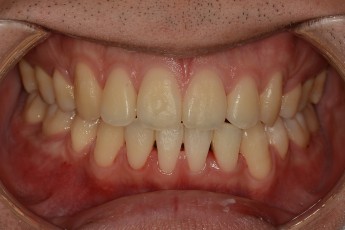

BEFORE & AFTER